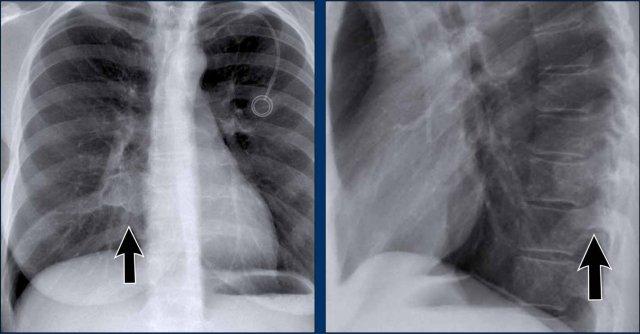

Thoát vị Bochdalek

- Thoát vị Bochdalek là một phát hiện tình cờ thường gặp ở người lớn, xuất phát từ khiếm khuyết cơ hoành phía sau (mũi tên).

- Thường chứa mỡ sau phúc mạc, không có triệu chứng và được phát hiện tình cờ.

- Trong các trường hợp hiếm gặp, các tạng ổ bụng có thể thoát vị vào lồng ngực.

- Ở trẻ sơ sinh, thoát vị Bochdalek lớn có thể dẫn đến thiểu sản phổi, có thể đe dọa tính mạng.

Thoát vị Morgagni

- Thoát vị Morgagni là một loại thoát vị cơ hoành bẩm sinh ít gặp hơn.

- Nằm ở phía trước, thường biểu hiện là khối sau xương ức bên phải.

- Giống như thoát vị Bochdalek, có thể không có triệu chứng hoặc chứa các tạng ổ bụng thoát vị.